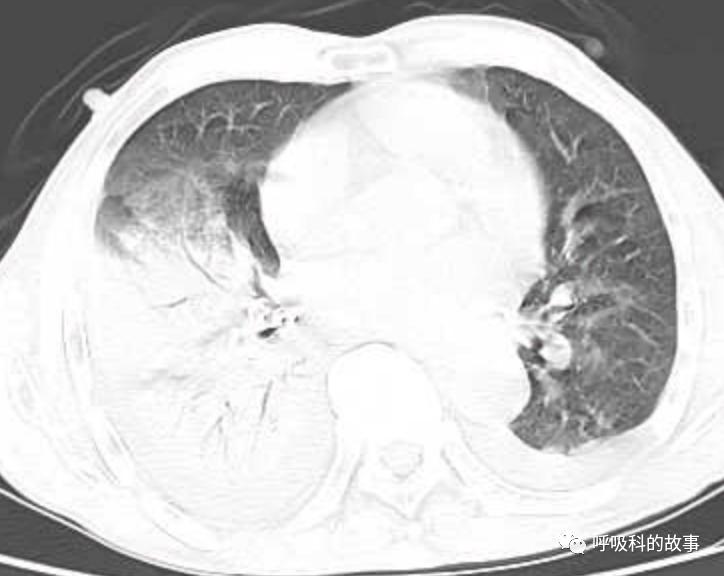

接着,我打开电脑看病历:患者,男,68岁,主诉:发热、头痛伴乏力10余天,咳嗽4天。肺部CT一看是右下叶大片实变肺炎,双侧少量胸腔积液,两上肺内中带片絮状斑片状影。2020.11.30 在外院检查 PCT 7.42ng/ml,ALT 199U/L,AST 250U/L,白蛋白24.7g/L,CRP 108.7mg/L,乳酸脱氢酶LDH388U/L(正常50-240),钾3.27mmol/L;血常规:白细胞4.9*10^9/L,中性85.2%。在外院给予了亚胺培南2天和本院美罗培南治疗2天后,效果并不理想。

(6)肺部影像以大叶性肺炎为主,其他部分是合并肺水肿的影像;